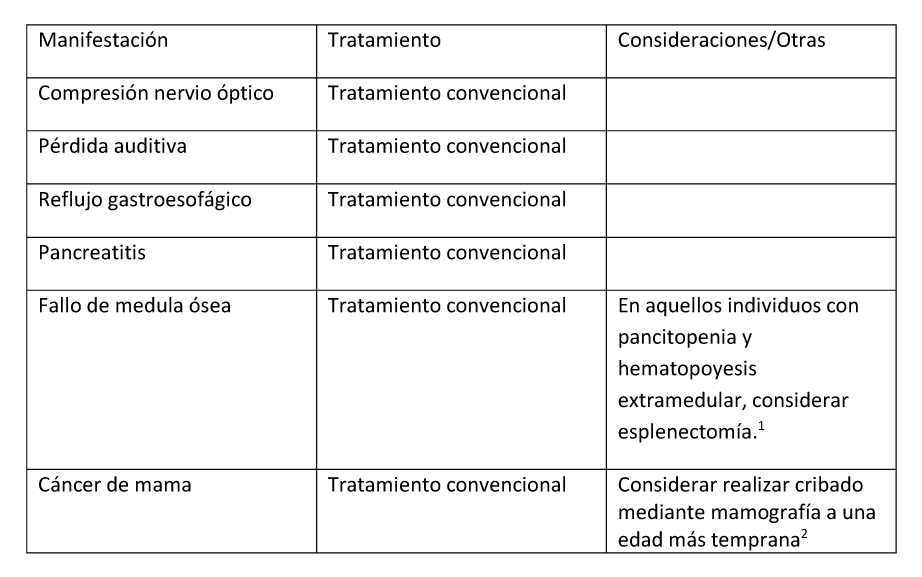

Mixomas

Se han identificado mixomas intramusculares benignos y asintomáticos de manera incidental.

Alteraciones hematológicas

Se han descrito casos de individuos con DF/MAS con insuficiencia medular con pancitopenia y hematopoyesis extramedular que han requerido una esplenectomía (Mahdi et al 2017, Robinson et al 2018).

Cáncer de mama

Es posible que el riesgo de cáncer de mama en mujeres con DF/MAS esté incrementado y que ocurra en edades más tempranas que en la población general. No obstante, la mutación patogénica en GNAS sólo se ha identificado en aproximadamente la mitad de los tumores de mama que han sido estudiados en mujeres con DF/MAS (Majoor et al 2018a).

Tabla 5. Tratamiento de Otras Manifestaciones en Individuos con Displasia Fibrosa/Síndrome de McCune-Albright

- Mahdi et al. (2017), Robinson et al (2018)

- Majoor et al (2018a)